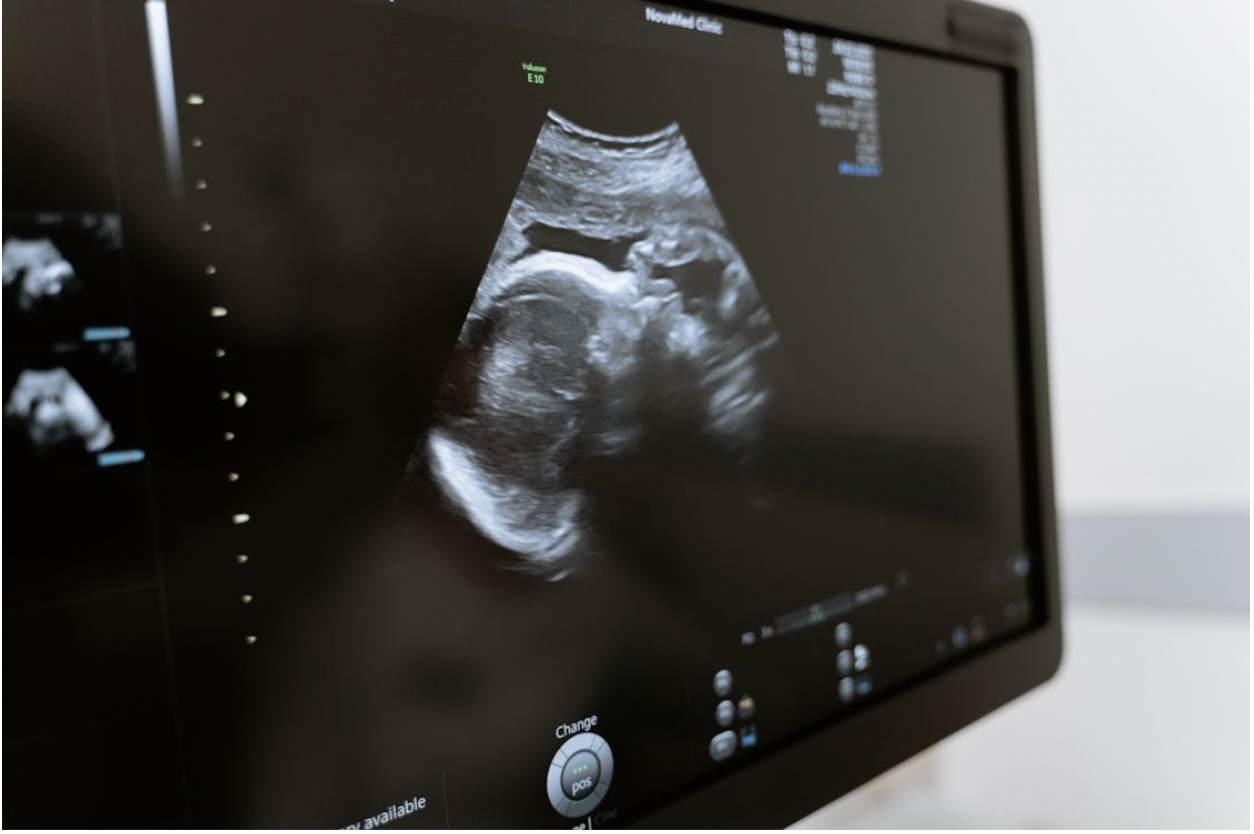

Ultrasound imaging uses sound waves to create images of the inside of the body. During pregnancy, it is primarily used to visualize the fetus, allowing healthcare providers to monitor its growth and development. The process is safe, utilizing no radiation, making it an ideal option for expectant mothers. Most expecting parents undergo at least one ultrasound in the first trimester to confirm the pregnancy, determine the due date, and check for multiple pregnancies. Conducted in a doctor’s office or hospital setting, the procedure typically lasts around 30 minutes.

A technician applies a gel to the abdomen to help the transducer slide easily over the skin, generating images on a screen. Patients can see their baby in real time, often capturing images that can be kept as cherished mementos. Many parents find this experience a bonding moment, bringing them closer to their baby early in the pregnancy. Accessing the best facilities, such as those providing innovative care with ultrasound solutions, enhances the quality of the imaging process significantly. Advanced ultrasound technology allows for clearer, more detailed images, helping doctors detect potential issues early. This early insight supports better prenatal care and reassures parents about their baby’s health and development.